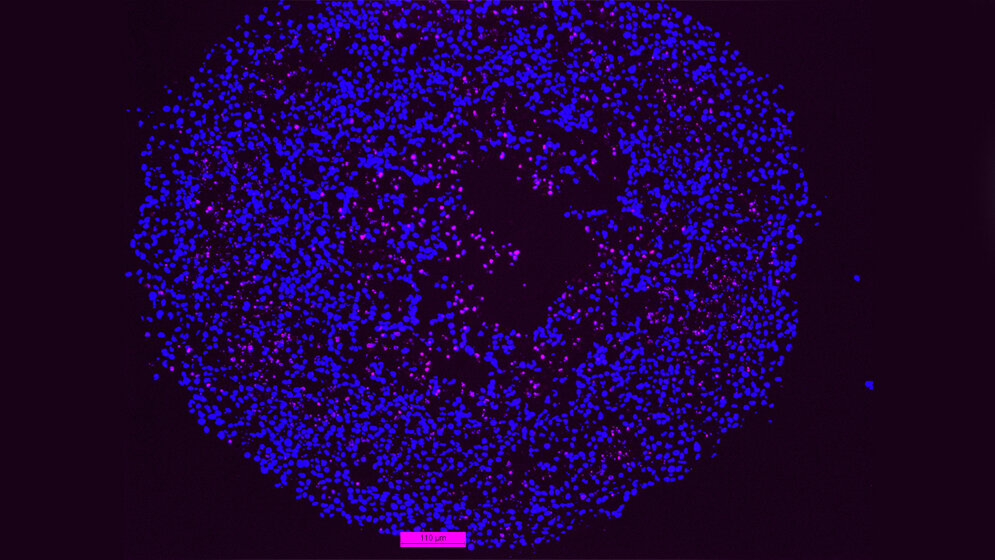

Um in der Kulturschale die Mangelsituation im Inneren einer Krebsgeschwulst zu simulieren, ließen die Forscher die Krebszellen zu kleinen Gewebekügelchen (Spheroide) heranwachsen. Darmkrebszellen mit intaktem p53 passten sich an die Mangelbedingungen im Inneren der Spheroide an, indem sie ihr Wachstum drosselten. Die Tumorzellen mit p53-Defekt dagegen wuchsen unbeirrt weiter. Dabei kurbelten sie einen Stoffwechselweg an, der die Versorgung mit dem wichtigen Zellmembranbestandteil Cholesterin ermöglicht, den so genannten Mevalonat-Weg.

Der Mevalonat-Stoffwechselweg lässt sich mit Statinen, gängigen Cholesterin-Senkern, hemmen. Und tatsächlich: Statinbehandlung löste unter den Mangelbedingungen im Inneren der p53-defizienten Mini-Tumoren den programmierten Zelltod – Apoptose – aus. Dagegen reagierten Mini-Tumoren mit intaktem p53 nicht auf die Medikamente.